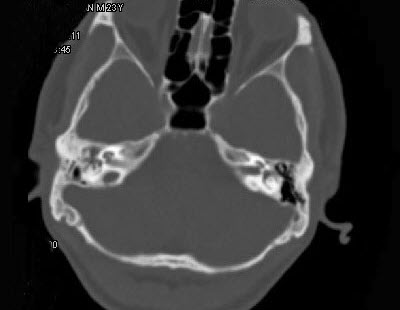

- 单项选择题男,23岁,右耳流脓十余年,右外耳道流脓,鼓膜穿孔,CT检查如图,最可能诊断为()。

A、慢性中耳乳突炎

B、中耳乳突结核

C、中耳癌

D、嗜酸性肉芽肿

E、海绵化期耳硬化症

- A